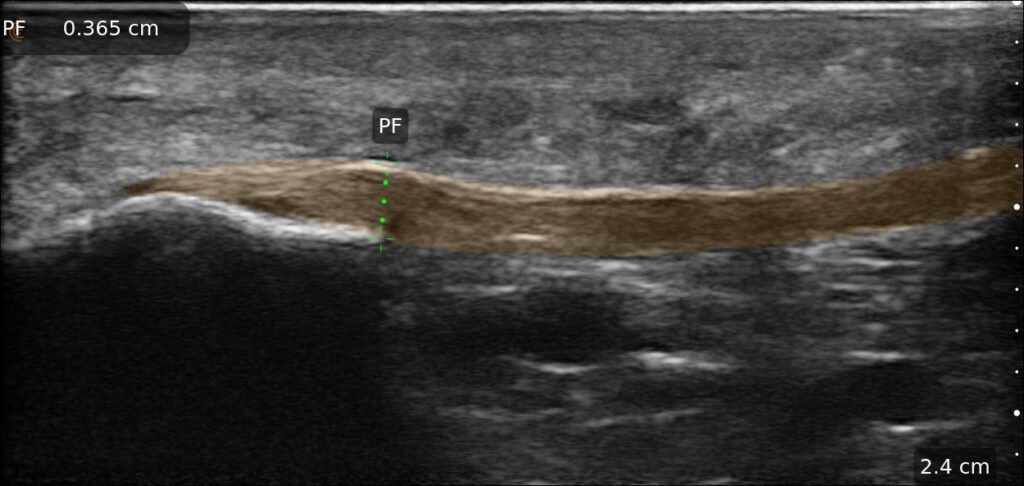

The Clarius L15 HD3 is the perfect probe for sports medicine.